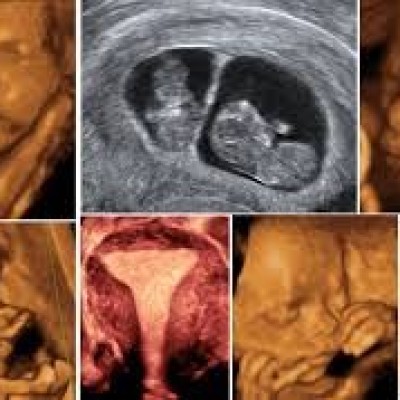

Advanced 3D & 4D Ultrasound helps parents see their baby’s face, movements, and expressions with greater clarity during pregnancy. It creates a special bonding experience while supporting detailed pregnancy monitoring in a safe and comfortable environment.

• Real-time baby movements

• Clear imaging of baby’s features